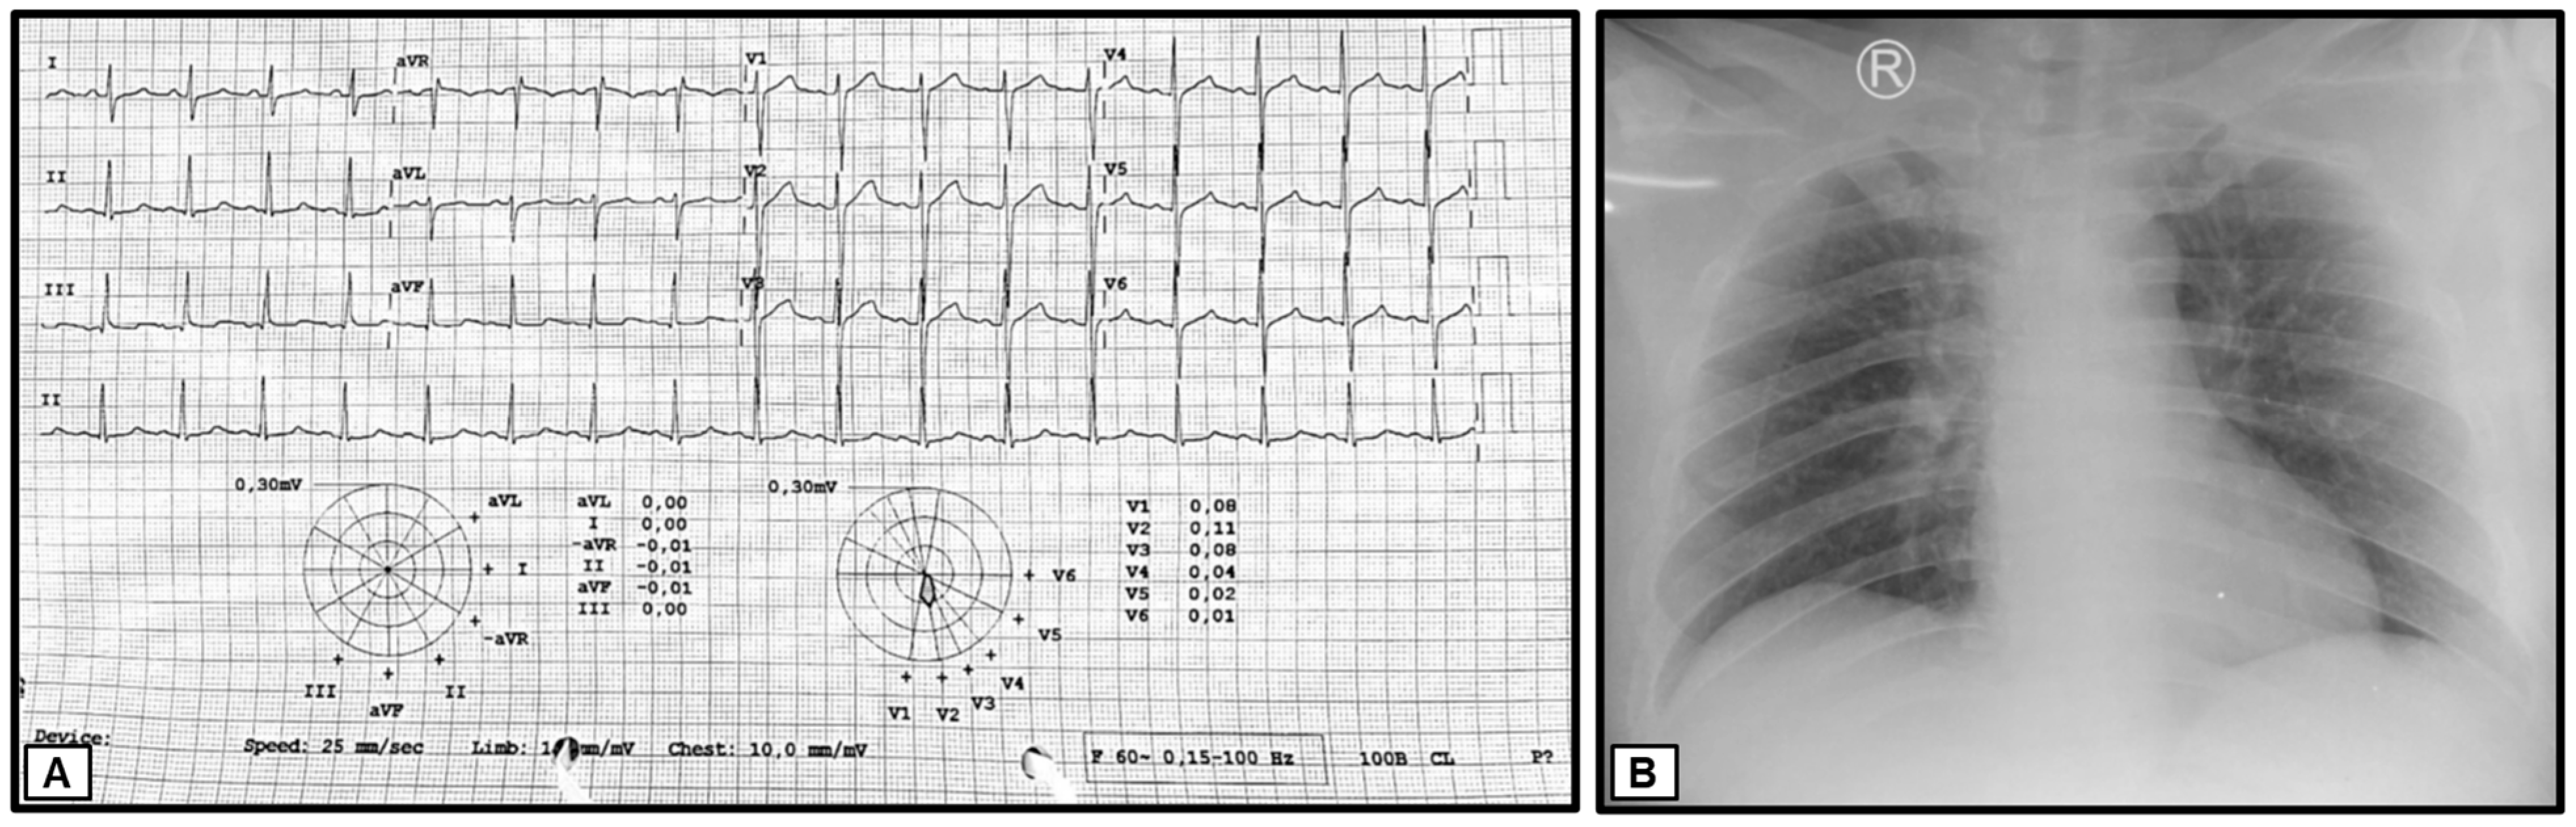

The preliminary laboratory examination conducted in the Emergency Unit revealed the following results: a hemoglobin concentration (Hb) of 18.2 g/dL, hematocrit (HCT) of 52.9%, leukocyte count of 10,000/μL with 64.9% neutrophils and 17.7% lymphocytes, and a platelet count of 298,000/μL. The random blood glucose (RBG) level was measured at 322 mg/dL, blood urea nitrogen (BUN) at 12.7 mg/dL, serum creatinine at 1.0 mg/dL, serum glutamic oxaloacetic transaminase (SGOT) at 16 U/L, serum glutamic pyruvic transaminase (SGPT) at 10 U/L, total bilirubin at 1.3 mg/dL, and direct bilirubin at 0.6 mg/dL. The serum albumin level was 4.18 g/dL, with sodium at 132 mmol/L, potassium at 3.5 mmol/L, and chloride at 94 mmol/L. Furthermore, the rapid human immunodeficiency virus (HIV) test, Hepatitis B surface antigen (HBsAg), and Hepatitis C virus antibody (anti-HCV) results were non-reactive. A chest X-ray examination revealed the thickening of the right hilum, indicating right hilar lymphadenopathy (Figure 3).

Figure 3.

(A) Electrocardiographic data showing normal results and (B) chest X-ray indicating right hilar lymphadenopathy.